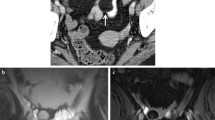

After NAT, the tumor may move away from anatomical landmarks or structures in a favorable manner. For instance, its inferior border may shift cranially making TME with a colo-anal anastomosis a possibility. Also, whenever a fat cushion becomes visible between the tumor bed and the mesorectal fascia at re-staging, or whenever the mesorectal fascia is reached only by very thin hypointense fibrotic spiculae, the specificity for a non-involved margin at pathology after TME may be 100% (Fig. 4.9a, b) [25]. On the other hand, whenever dense hypointense “fibrosis” reaches the mesorectal fascia, a resection beyond TME plane should be planned to achieve negative margins (Fig. 4.9c, d) [25].

Staging (a) and 11 weeks post-NAT re-staging (b) MR oblique axial T2-weighted images depicting a low rectal cancer. The tumor reached and pushed the right levator laterally at staging examination (arrow in a). After NAT, it regressed, and a thin fat plane became visible between it and the levator (arrow in b). Patient underwent abdominoperineal excision and an ypT2N0R0 specimen was obtained; another case of a very low rectal tumor invading the posterior wall of the vagina and the left levator at staging examination (arrows in c). Twelve weeks post-NAT, it regressed but a relatively large surface of contact between the hypointense fibrotic tumor bed and the posterior wall of the vagina was still apparent (arrow in d). Anteriorly extended abdominoperineal excision specimen showed a ypT3 tumor <1 mm from the anterior mesorectal fascia